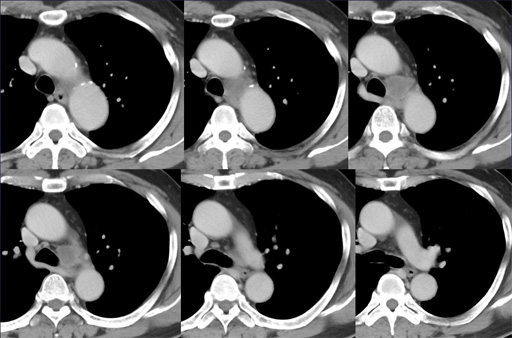

症例7 : 図3 胸部CT 縦隔条件